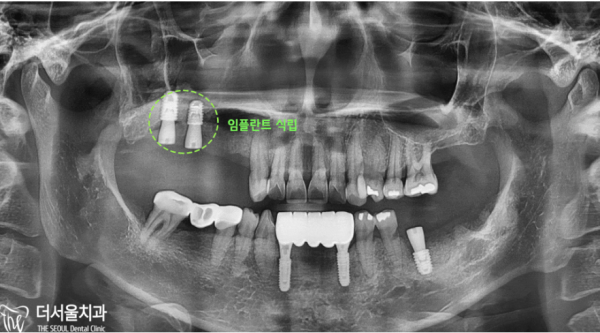

이 환자분은 어금니를 발치하고 시간이 오래되신 분이신데요.

임플란트를 심으려 했지만 쉽지 않다는 이야기를 들으시고, 저희 태평역치과 더서울치과를 찾아주셨습니다.

보이시는 것 처럼 치축이 앞으로 쏠려있고, 앞니도 뿌리가 많이 드러나 있었습니다.

그리고 어금니를 보시면 잇몸뼈가 녹아서 골폭이 줄어들어있습니다.

This patient has had his molars removed for a long time.

After hearing that it was not easy to plant implants, he visited our Taepyeong Station Dental Clinic The Seoul Dental Clinic.

As you can see, the teeth are leaning forward, and the front teeth are also showing a lot of roots.

And if you look at the molars, the gum bones are melted and the bone width is reduced.